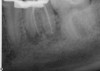

Excellent diagnosis essentially begins with two fundamental components: a doctor willing to listen to the patient’s chief complaint, and proper diagnostic tools. Among the most important tools are a precise periapical radiograph (PA) and bitewing (BW). Although a PA is often enough to provide an accurate portrayal of the patient’s condition, sometimes it alone does not suffice. Figure 1, Figure 2, and Figure 3 demonstrate a case that illustrates this point clearly. Despite two acceptable PAs (Figure 1 and Figure 2), it is difficult to assess the source of the patient’s pain to temperature. However, the BW radiograph Figure 3 provides significantly more clarity than either of the two PAs. The BW depicts localized bone loss (around tooth No. 2), a pulp stone (No. 2), a flat occlusion, numerous calcified canals, multiple restorations in tooth No. 30, and gross decay especially on tooth No. 3, which is the source of the patient’s pain to temperature. In this instance these images depict how much more useful a BW can be than just a conventional PA.

Fig 3. BW of the same upper right area as shown in Figure 1 and Figure 2, depicting gross decay not visualized on prior PAs.

Figure 3